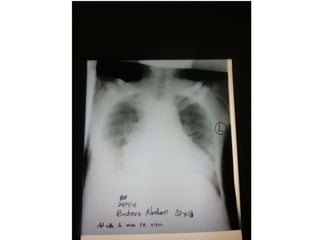

• Chest x-ray

Investigations • Chest x-ray •Urinalysis • ECG • CBC